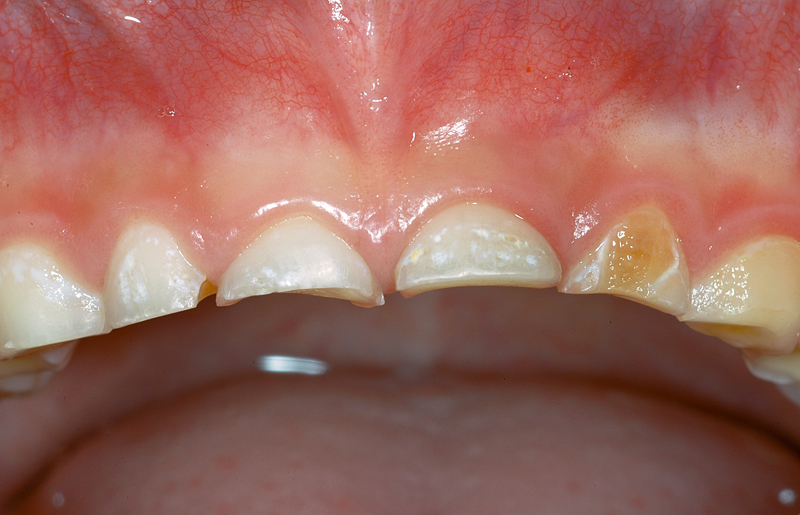

Hier ein Fall mit einer Karies auf der Aussenfläche (Bukkal-Fläche) des linken seitlichen Milchschneide-Zahnes (Zahn 62); das ist die braune, flächige Verfärbung.

Im Zahnzwischenraum «vorne» (mesial) am gegenüberliegenden Zahn 52 ist ebenfalls eine Karies sichtbar.

Ein solches Bild mit Karies an den Glattflächen ist nicht untypisch für die so genannte «Flaschenkaries», verursacht durch ständiges Schoppentrinken oder Nuckeln an Süssgetränken.

Zudem ist bei diesem etwa 7½ Jahre alten Patienten auffällig, dass noch alle Schneidezähne vorhanden sind (verspäteter Zahnwechsel) wie auch, dass die Zähne sehr kurz sind. Das kann z.B. auf «übermässigen Gebrauch» (Knirschen) zusammen mit einer dies begünstigenden Zahnstellung (Kopfbiss) zurückzuzuführen sein, was zur so genannten Abrasion der Zähne führt.

- Karies an 62